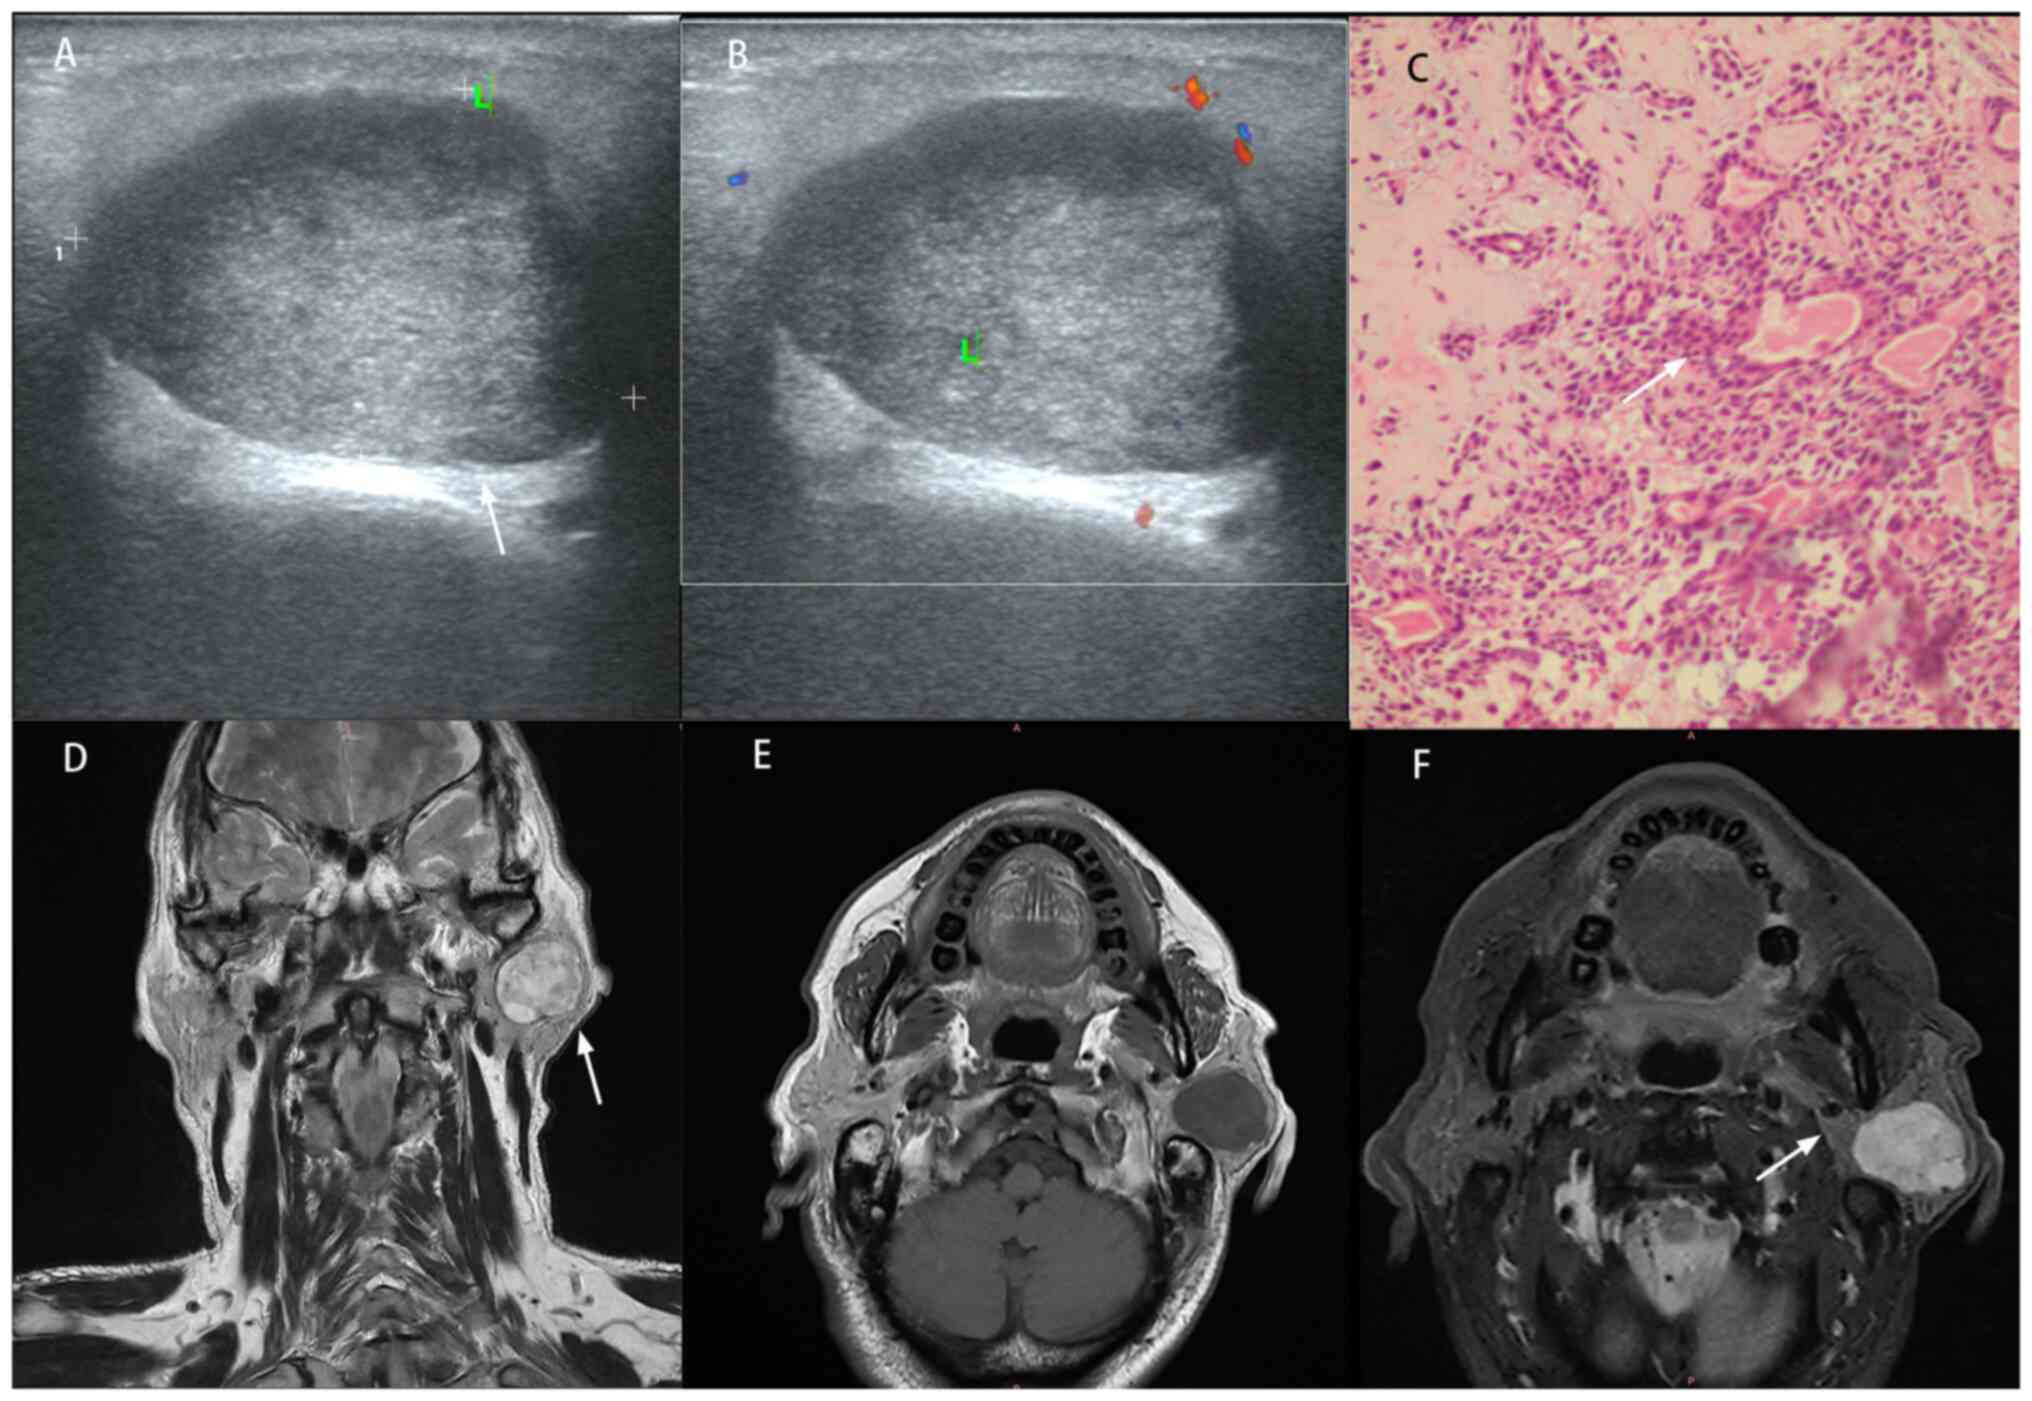

Features of pleomorphic adenoma on

US, MRI and histopathology. (A) US: Regular contours,

well-circumscribed margins (arrow) and mild hypoechogenicity. (B)

Color Doppler: Homogeneous architecture without detectable

vascularity. (C) Histopathology (H&E stain): Confluent sheets

of epithelial/myoepithelial cells embedded in chondromyxoid stroma

(arrow). (D) Coronal T2-weighted MRI: Well-defined margins (arrow)

with dominant hyperintensity admixed with hypointense foci. (E)

Axial T1-weighted MRI: Heterogeneous hypointensity. (F) Short Tau

Inversion Recovery sequence: No abnormal lymph nodes (arrow). US,

ultrasound.

Figure 3

Features of pleomorphic adenoma on US, MRI and histopathology. (A) US: Regular contours, well-circumscribed margins (arrow) and mild hypoechogenicity. (B) Color Doppler: Homogeneous architecture without detectable vascularity. (C) Histopathology (H&E stain): Confluent sheets of epithelial/myoepithelial cells embedded in chondromyxoid stroma (arrow). (D) Coronal T2-weighted MRI: Well-defined margins (arrow) with dominant hyperintensity admixed with hypointense foci. (E) Axial T1-weighted MRI: Heterogeneous hypointensity. (F) Short Tau Inversion Recovery sequence: No abnormal lymph nodes (arrow). US, ultrasound.